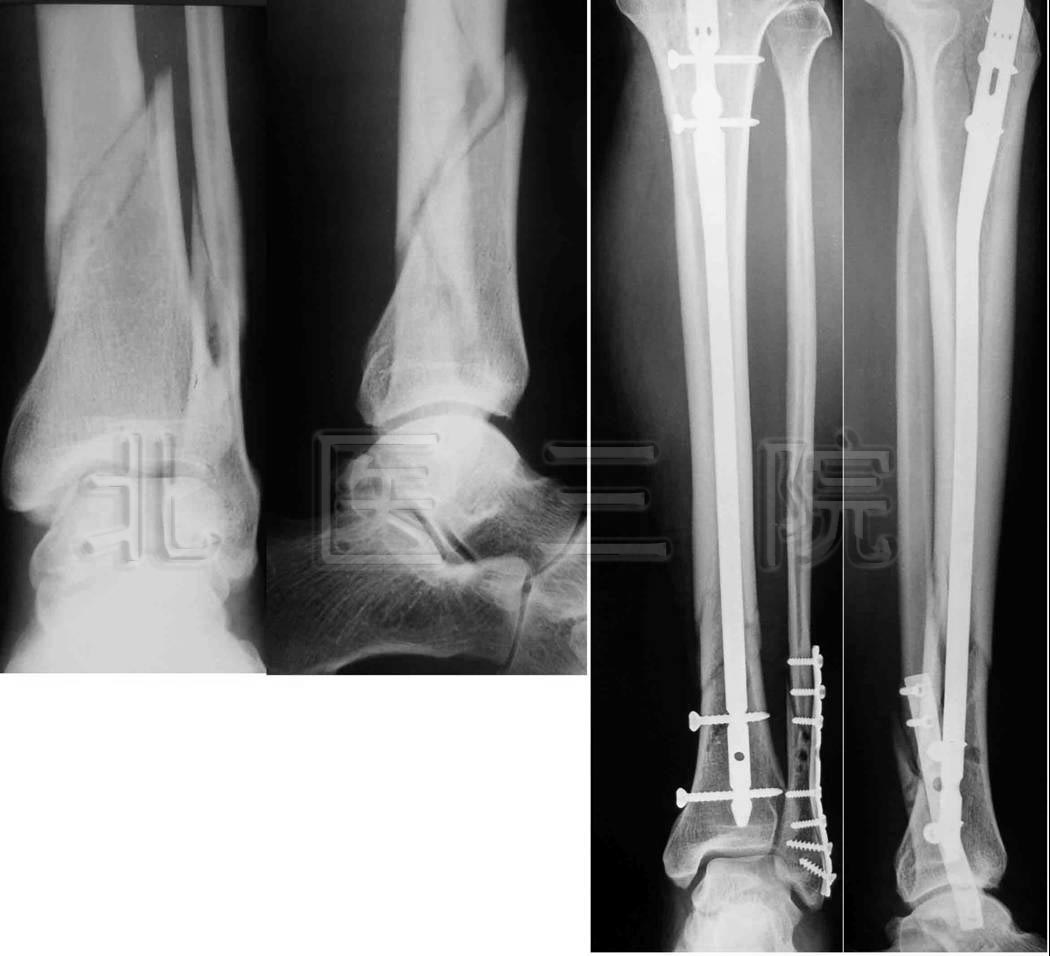

4.男,35岁,车祸致多发创伤

1)股骨上端骨折

2)胫腓骨下端粉碎性骨折

3)L1、L2骨折

5.女,66岁,外伤致股骨下端骨折,行股骨逆行交锁髓内

钉固定术

6.女,43岁,车祸致胫骨平台骨折

7.男,49岁,胫腓骨骨折,径胫骨髓内钉固定+腓骨钢板固定

8.男,44岁,高处坠落伤致左髋臼、骨盆骨折

9.男,55岁,高处坠落伤致跟骨骨折